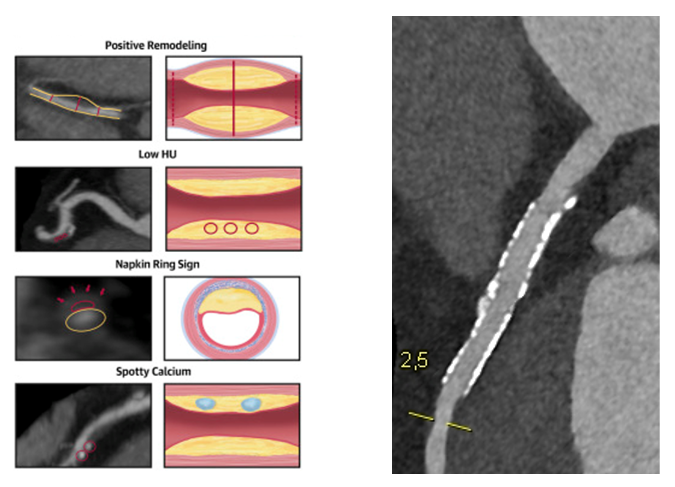

• Beschreibung von kalzifizierten, nicht-kalzifizierten und gemischten Plaques unter Verwendung von Rekonstruktion (Darstellung verschiedener Ebenen: axial, sagittal, koronal und multiplanar; s. Abbildung 1). Erwähnung von „High-Risk-Plaque“-Charakteristika wie positives Remodeling, „low attenuation plaques“, „spotty calcifications“ und „napkin ring sign“ (s. Abbildung 2).

Hochrisikomerkmale zur genaueren Plaque-Charakterisierung / Frei perfundierter Stent in der proximalen LAD mit Ausschluss einer In-Stent-Restenose mittels Photonen-Counter Technologie Abb. 2 (links): Hochrisikomerkmale zur genaueren Plaque-Charakterisierung („high-risk-plaques“), Puchner et al., JACC 2014. Abb. 3 (rechts): Frei perfundierter Stent in der proximalen LAD mit Ausschluss einer In-Stent-Restenose mittels Photonen-Counter Technologie (Naeotom Alpha PCCT).